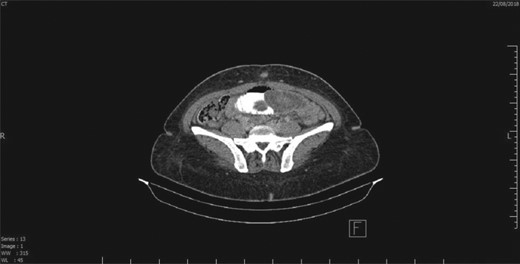

CT scan showing a segment of intestine telescoping into another, which is suggestive of intussusception.

This is a case of a 46-year-old female, 3 years post REYGB. She presented to the emergency department with sudden abdominal pain as well as nausea and vomiting, which started the day before presentation (30 minutes post prandial). Moreover, on physical examination, the abdomen was soft with pain out of proportion (severe pain with minimal tenderness) and no other signs of peritoneal irritation. Furthermore, laboratory data were unremarkable. Abdominal computed tomography (CT) revealed a long segment of obstructed retrograde small bowel obstruction adjacent to the jejuno-jejunal anastomosis associated with a complete proximal small bowel obstruction (Fig. 1). Therefore, the patient was immediately taken to the operating room, and laparoscopic exploration of the abdomen was performed. A segment of retrograde jejuno-jejunal intussusception was encountered with dilated small bowel proximal to the intussusception and a collapsed part distal to it. Decision was made to convert the procedure to an open surgery through a small midline laparotomy (Fig. 2), and a trial was performed to undo the intussusception. There was a gangrenous segment of about 23 cm, necessitating resection and anastomosis (Fig. 3). The anastomosis was performed using a gastrointestinal anastomosis stapler device. Consequently, the patient tolerated the procedure well, and she was sent for recovery in a good condition. Pathology confirmed a gangrenous jejunal segment with features consistent with external venous compression (intussusception related) with viable surgical resection margins. Afterwards, the patient was discharged on postoperative day 3 in a good condition, and she remained asymptomatic during the follow-up period of 1 year.